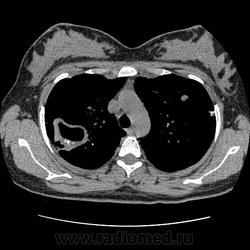

Ага, сначала вот эта с каверной пришла 12.05, а потом с туберкуломами 19.05 с интервалом в неделю, закон парных случаев, обе только родили, род.дом в панике, я в шоке

В том то и дело, что анамнез скудный, жалоб нет или врала, жила себе поживала девушка, забеременела, родила, а в правом легком "дырка".